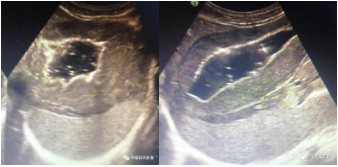

“连根”溃疡:胃和十二指肠均见溃疡,并且溃疡之间黏膜下层低回声相连。

左图:胃淋巴瘤“浸水征”:胃淋巴瘤向外侵犯胰腺,侵犯的胰腺回声减低,轮廓未改变,像干枯的土地被部分浸水;

右图:胃癌侵犯肝脏,侵犯的肝脏表现为缺失一部分正常肝组织,表现为“咬饼征”。